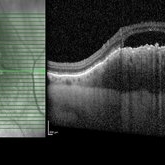

Plateau Fovea with Inner Retinal Thinning

May 27 2020 by Olivia Rainey

Optical coherence tomography of the left eye of a 20-year-old male with Alport Syndrome. The patient did not present with any ocular or visual symptoms, yet the distinct "plateau contour" of his fovea was noted on OCT during his visit. The patient presented with 20/25 vision at the time of his visit. There was myelinated nerve fiber layer noted in both eyes, but these features had remained stable from his appointment three years prior. The physician noted that myelinated nerve fiber was a congenital change, and had not affected his vision or health of the eye, nor is a feature of Alport Syndrome.

Photographer: Olivia Rainey, OCT-C, COA

Imaging device: Heidelberg Spectralis

Condition/keywords: Alports disease, Heidelburg Spectralis, inner retinal thinning, left eye, optical coherence tomography (OCT), plateau fovea